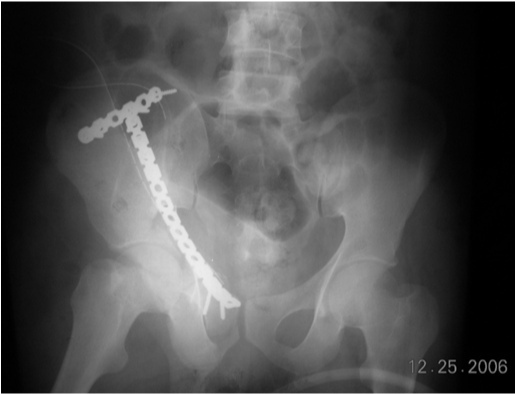

All patients were initially evaluated with use of three standard plain radiographs (one anteroposterior radiograph and two 45-degree oblique radiographs of the pelvis).2 Computerized tomographic scans and three-dimensional reconstructions of the scans were made for all patients. The displacement of the fracture was measured separately. The maximum displacement seen on each of the three radiographs was recorded. The fractures were classified according to the criteria of Letournel and Judet3 of the 28 fractures, six fractures (21 per cent) were simple fracture types and twenty two (79 per cent) were associated fracture types. The simple fracture types included five posterior wall fractures (18 per cent) and one anterior column fractures (4 per cent). The associated fracture types included seven posterior column-posterior wall fractures (25 per cent), four transverse-posterior wall fractures (14 per cent), one T-shaped fractures (4 per cent), and ten both-column fractures (36 per cent). Seven hips had a posterior dislocation and one had an anterior dislocation. All eight hips were reduced before the operation. Preoperative below knee skin traction was used in all patients (Figure 1).

Figure 1 Preoperative radiograph showing anterior column fracture acetabulum.